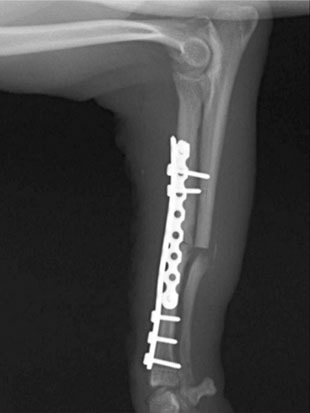

ペルシャ猫 11ヶ月齢 雄

他院にて左大腿骨遠位の成長板骨折(salter-harrisⅠ型)が認められており、治療相談を目的として来院。当院にて、キルシュナーワイヤーを用いたピンニングにより骨折部位の整復を行いました。術後の経過は良好で、現在も経過観察中です。

術後レントゲン

Arthrex社のターゲティングデバイスを用いてピンニングの位置を調整することで、確実な固定を行っています。当院ではこの手術器具以外にも、人の手術にも使用される様々な器具を導入し、手術精度を高め、また医療メーカーと新しい器具の開発、試作にも取り組んでおります。